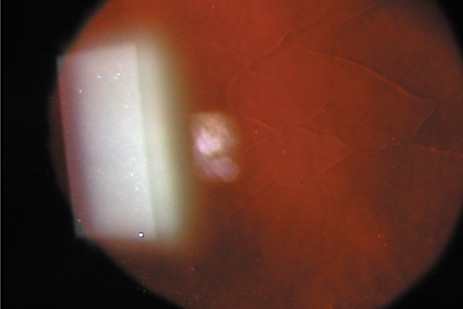

In the past, the only options for removal of corneal opacities were lamellar or penetrating keratoplasty. With the use of the excimer laser, some superficial opacities can be removed without the need for more invasive surgery. Figures 5 and 6 show examples of corneal opacities treated with PTK, resulting in marked improvement in central corneal clarity. Maloney and coworkers reported the results of 232 patients treated with PTK for corneal visual loss (resulting from opacities, surface irregularity, or both) in a prospective, multicenter trial.68 Approximately 45% of patients at each follow-up visit experienced a two-line improvement of best corrected vision. Other studies have revealed similar results.69–72

Fig. 5. A. Preoperative appearance of a patient with the granular appearance of the Avellino variant of lattice dystrophy. Most of the opacities are superficial. B. Four days after excimer ablation, re-epithelialization has occurred. Most of the opacities are eliminated from the treatment zone. C. One month after surgery, dramatic improvement in central corneal clarity has occurred. (Steinert RF: Therapeutic keratectomy: Corneal smoothing. In Thompson FB, McDonnell PJ [eds]. Color Atlas and Text of Excimer Laser Surgery. New York: Igaku-Shoin, 1993:179)

Fig. 6. A. Herpetic anterior stromal scar before excimer phototherapeutic keratectomy. B. Appearance immediately after excimer phototherapeutic keratectomy, with reduction of the stromal scarring. The edge of the 4.5-mm–round ablation zone is evident. C. Three months after surgery, an oblique slit illumination shows some persistence of the deeper herpetic scarring plus the addition of reactive reticular haze. At this time, however, acuity was 20/30 versus 20/80 before surgery.